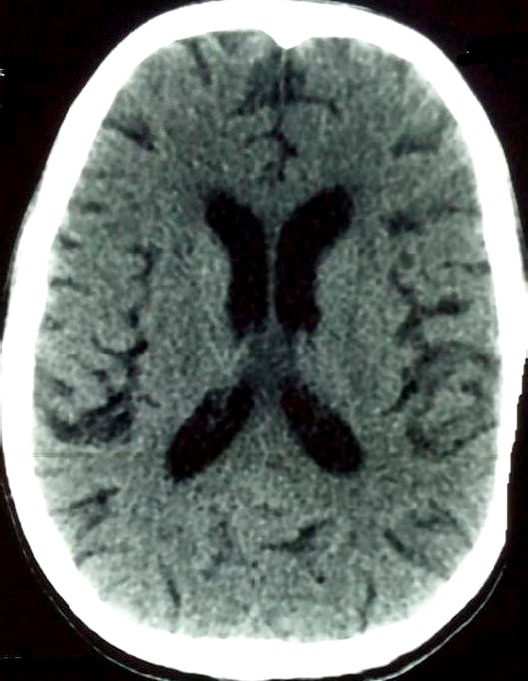

Case description: The patient presented with fever (39.3°C), general deterioration, Glasgow Coma Scale score of 10/15 without motor deficits, neck stiffness, and helmet-like headache unresponsive to analgesics. The patient had a CD4 count of 932 cells/mm3. No other immunosuppressive conditions were noted. The diagnosis of NMC was confirmed based on clinical and microbiologic findings. The patient was successfully treated in Bamako using an alternative protocol with fluconazole, a more accessible, less expensive treatment with fewer side effects compared to amphotericin B.

Abstract Image